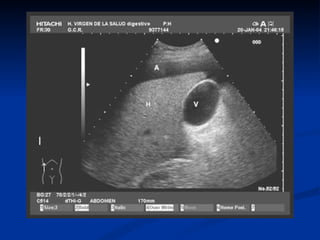

Diagnóstico por Imágenes.

   Ecografia.

   Eco-Doppler.

   T.A.C.

   R.M.N.

Ecografía

   Es el método de elección.

   100 ml de líquido ascítico.

Goldberg BB, Goodman GA, Clearfield HR. Evaluation of ascites by ultrasound. Radiology

1970;96:15-22.